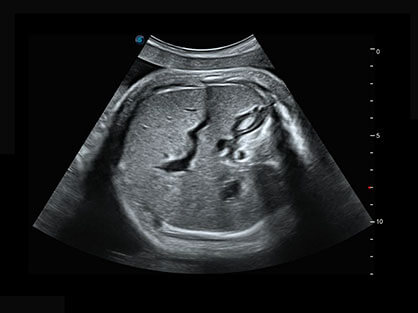

作为P系列家族成员之一,P40 Plus采用玖鼎集团高端超声系统平台——极光,并以时尚秀丽、小巧灵动的外观设计绽放出灵动之韵、科技之美。高端平台的使用保证了P40 Plus优质的基础图像;完备的高级功能可满足您全身应用的基本需求;丰富的探头配置、多样的高级4D成像及分析软件为您日益增多的妇产应用需求提供丰富的诊疗方案。

自动获取标准切面,自动完成测量,帮助医生快速完成检查,同时提升测量准确性。

宽频带腹部凸阵探头和腹部容积探头、大角度腔内探头和腔内容积探头、独特的生殖专用曲柄探头,为妇产应用提供全面诊疗方案。